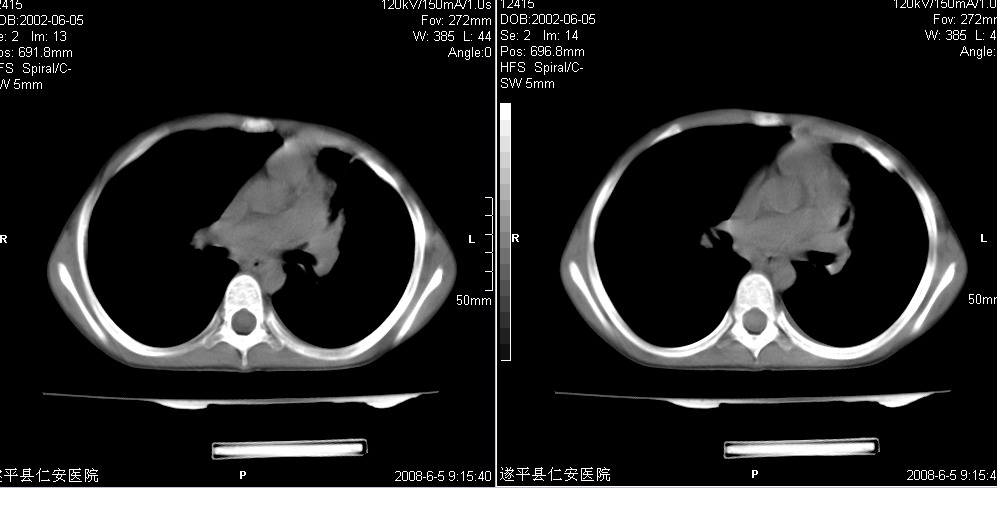

以下是引用xxhwh在2008-6-10 18:40:00的发言:[br]男,6岁,无规则发热一月余,体温在37.8——39度之间。一月前拍胸片示左上肺密度增高影,进行抗炎治疗8天,复查胸片未明显吸收。又改变抗菌素继续治疗半月,照胸片示病灶吸收不明显,行ct检查[br]征象:左上肺前段呈密实影,内可见支气管气像,远侧见絮状模糊影,中上纵隔左移。[br]意见:左上肺前段膨胀不全及感染,考虑为支气管异物或支气管内膜结核所致,[br]建议追问有无异物吸入史,行痰检及ppd检查